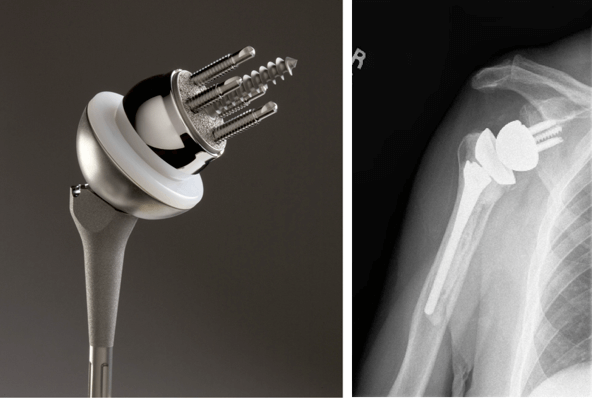

Имплантаты на ножке по своему строению могут быть анатомическими и обратными. Анатомический состоит из трех частей: головка, ножка и впадина. Назван так, поскольку полностью повторяет структуру человеческого плеча и по биомеханике, и по форме.

Установка такого протеза возможна только в том случае, если вращательная манжета не повреждена. При замене используется продукция таких мировых производителей как DePuy, Zimmer, Smith&Nephew, Biomet, Aesculap — B. Braun.

Обратный или реверсивный используется, когда вращательная манжета не функционирует и нарушена стабильность. Тогда головка крепится к суставной впадине (гленоидальному компоненту), а вогнутый имплантат впадины на ножке фиксируется на плечевой кости.

Для однополюсного эндопротезирования используются гемипротезы, то есть заменяющие только одну часть сустава. По способу установки делятся на поверхностные и штыревые (внедряются в кость).

Также имплантаты могут быть цельными или сборными (модульными). Модульные позволяют за счет подбора различных размеров элементов корректировать при необходимости положение плеча. Существуют следующие способы крепления протезов к кости:

- бесцементный. Фиксация производится «вколачиванием». Подходит для имплантации в плотную костную ткань, способную надежно удерживать ножку;

- цементный. Ножка закрепляется с помощью специального раствора. Используется при недостатке или плохом качестве собственной костной ткани.

Ревизионное эндопротезирование в случае обширного поражения тканей, замены эндопротеза или сильного разрушения кости требует специального имплантата, который частично компенсировал бы функциональную недостаточность мышц. Например, Delta XTEND производства компании DePuy. Центр ротации у него смещен вниз и кнаружи, что увеличивает диапазон движений, сохраняя при этом стабильность сустава.